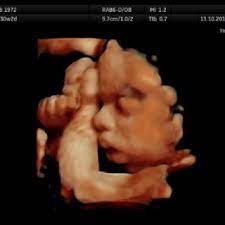

At this stage, the baby has put on some weight and filled out to make features more visible, yet still enough fluid in front of baby's face to obtain great images. I'm only at 31 weeks, but i had that 4d/3d u/s and yes, baby looked totally deformed. We just went yesterday at 31 weeks 4 days. In fact, it's quite similar to 4d ultrasound. Up to 32 weeks there generally still room for the baby to move. View images & learn more 30 week ultrasound The 4d ultrasound uses sound waves to create this moving image. Sofort kostenlos und ohne anmeldung anfragen

It is a fun time for the ultrasound as many times you will see movements like smiling, eyes blinking, hands moving, and many other movements. If you are having multiples this is also a good time to capture 3d pictures of the babies. At this stage, the baby has put on some weight and filled out to make features more visible, yet still enough fluid in front of baby's face to obtain great images. Your baby has to hold very still so that the high frequency sound waves have time to form around your baby's features. Snuggling cord at 18 weeks. The 4d ultrasound uses sound waves to create this moving image. Up to 32 weeks there generally still room for the baby to move. Baby impressions is an elective 3d 4d ultrasound imaging facility. At 18 weeks, your baby has mastered the art of yawning, along with hiccuping, which you may feel soon. You learn today about your baby development, prenatal care (doctor visits) and fetal ultrasound at 31 weeks. I'm only at 31 weeks, but i had that 4d/3d u/s and yes, baby looked totally deformed. Sounds like you have a very active baby! We require that all mothers have documentation of their prenatal care and most recent diagnostic ultrasound.

Come and see for yourlself. The best proof is our gallery of weekly 3d ultrasound images taken from 13 weeks and until up to 39 weeks. This page shows typical 3d ultrasound images from 11 to 36 weeks. All 3d ultrasound photos were taken in greenville sc at baby impressions. 18 week hd live/4d ultrasound. 3d/4d ultrasound march 31, 2021 | by kamrynlea has anyone gotten a 3d/4d ultrasound around 26/27 weeks? (so 31 weeks pregnant is the perfect time!) We do not perform medical ultrasounds. I have one scheduled and want to see some pics of what to expect!! At this stage, the baby has put on some weight and filled out to make features more visible, yet still enough fluid in front of baby's face to obtain great images. You're just dying to know what baby looks like inside your 31 weeks pregnant belly. Yawns, stretches, and even smiles are often captured in our 3d & 4d ultrasounds, and we look forward to sharing this miracle with you as well! Snuggling cord at 18 weeks.